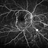

- hemicentral retinal vein occlusion, collaterals, retinal neovascularization

- Initial presentation: 25-year-old AAM; Hx DM, Sarcoidosis, Renal Disease, HTN with recent hypertensive crisis. Collateral vessels likely due to old HRVO with one front of NVE inferiorly; veins attenuated proximal to the collateral vessels.